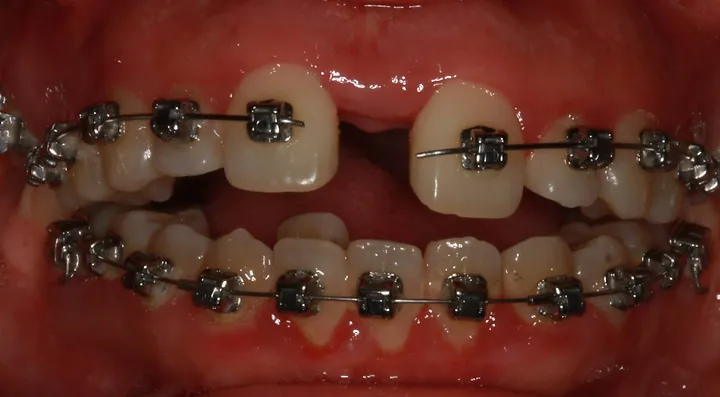

87f545_bc43680091984bbdb74de17eb337bbfd~mv2_d_1920_1280_s_2.webp

87f545_f42d29ecf80a4b9fa8b3f13471579528~mv2_d_1920_1280_s_2.webp

87f545_1c85956a5c2243d1acfc7176f18e69a7~mv2_d_1920_1280_s_2.webp

87f545_91b464f1d91749a39ae126d3341b6d30~mv2.webp

look how the maxilla was ripped apart on this one holy chit